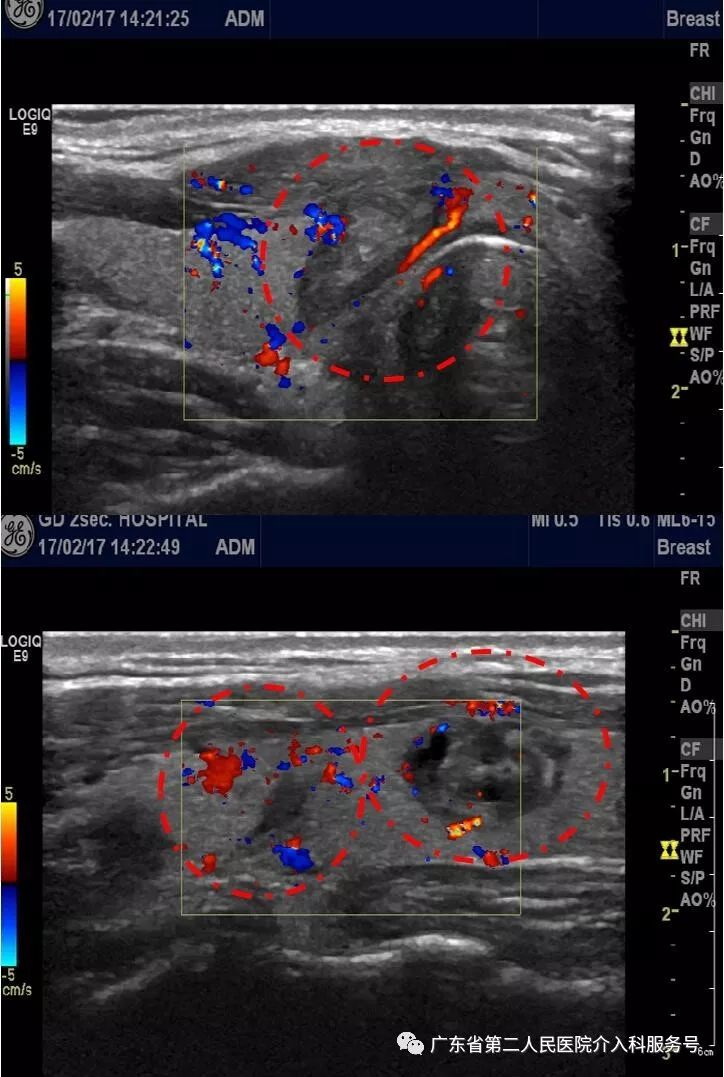

康女士微创介入消融后1个月复查甲状腺功能正常,超声显示3个甲状腺结节完全消融,最大的甲状腺结节明显缩小到两公分(如下图)。

康女士微创介入消融后3个月复查超声显示3个甲状腺结节进一步缩小,最大结节缩小至1.6公分(如下图)。